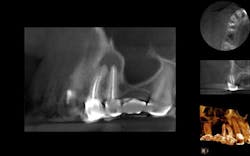

Nonsurgical endodontic retreatment with the aid of cone beam (CBCT) imaging

Endodontic therapy under current treatment protocol shows long-term clinical success rates of 86% to 92%. Even with the high clinical success rate of initial endodontic treatment, it’s obvious to see this leaves clinicians with a 14% incidence (on the high side) of encountering post-treatment disease. Dr. Brian McCormack presents a case that was treated with the aid of CBCT imaging and a surgical operating microscope. Click here to read the article.